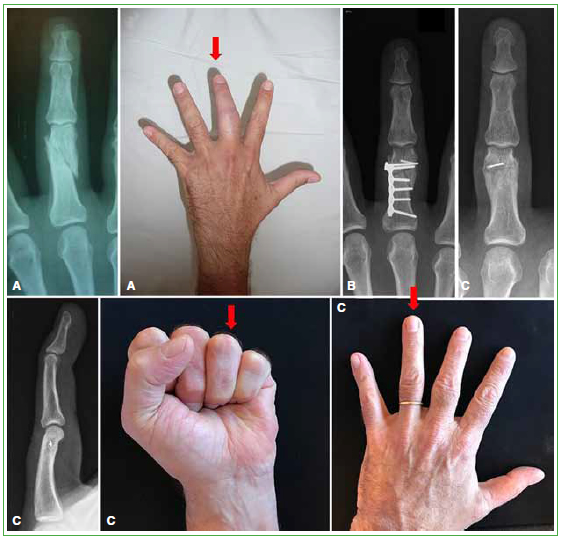

Objetivo: Evaluar los resultados y las complicaciones de una serie de pacientes con consolidación viciosa de falange. Materiales y Métodos: Se realizó un estudio retrospectivo que incluyó a pacientes con consolidación viciosa de falange tratados mediante osteotomía en el sitio de la deformidad, estabilizados con osteosíntesis rígida. Se registró la movilidad de los dedos. La valoración subjetiva consistió en el puntaje DASH y una escala analógica visual para el dolor en reposo, en actividad y la función. Resultados: Doce pacientes (13 falanges) cumplieron los criterios de inclusión. El tiempo promedio entre la lesión inicial y la osteotomía fue 14 meses y el seguimiento promedio, 34 meses. La movilidad final promedio en flexo-extensión fue 89° metacarpofalángica, 74° interfalángica proximal, 54° interfalángica distal y la distancia pulpejo-palma, 3 mm. El puntaje promedio de la escala analógica visual en reposo fue 0; en actividad, 1 y la función promedio fue de 7 puntos; el puntaje DASH promedio fue 6. No hubo casos de seudoartrosis. Cinco pacientes requirieron el retiro de la placa. Los pacientes con osteotomía articular no presentaron signos de artrosis. Conclusiones: La osteotomía de falange en el sitio de la deformidad es un procedimiento eficaz con un buen resultado objetivo y subjetivo a corto plazo. La utilización de placas y tornillos conlleva una tasa más alta de complicaciones; por lo tanto, los pacientes deben ser advertidos sobre la posibilidad de una segunda intervención quirúrgica.Descargas